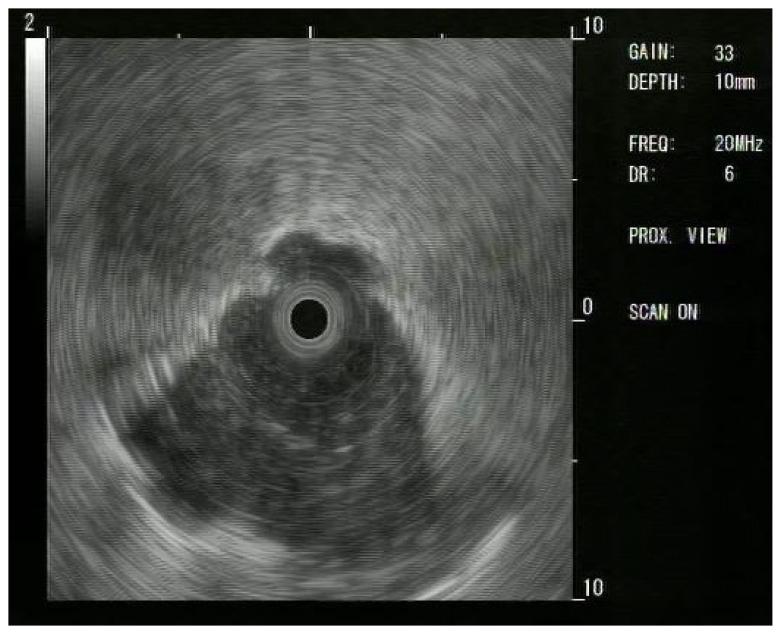

Peripheral pulmonary lesions (PPLs) are the current challenge in bronchoscopy. Novel endoscopic approaches allow us to reach PPLs better than a few years ago. In patients with resectable non-small cell lung cancer (NSCLC), perioperative chemotherapy is associated with significantly greater event-free survival; this means that histological assessment before the resectable surgery of PPLs is becoming mandatory. Our objective was to evaluate the diagnostic yield (DY) of a thin bronchoscope (TB) for PPLs suspected for lung cancer that are not reachable with conventional bronchoscopy. A total of 176 patients with PPLs were evaluated from January 2022 to July 2023. Of the patients, 26 presented with not reachable PPLs with conventional bronchoscopy, and underwent the procedure again with a TB. When possible, R-EBUS was used. PPLs' dimensions were recorded via chest computed tomography (CT) scan. DY was evaluated. Mean lesion size was 29 mm, and overall DY for TB was 65% (17/26). When the lesion was bigger than 20 mm, DY was 76.5% (13/17), whereas in lesions smaller than 20 mm, DY was 55% (5/9). When PPLs presented a bronchus sign in the CT scan, diagnostic performance of TB was significantly better (76.5% vs. 40%, p = 0.04) compared to PPLs without a bronchus sign, independent from PPL dimensions. R-EBUS did not change DY. TB easily allows us to reach and sample PPLs with a high DY if a bronchus sign is positive, independently from PPL dimensions. Further studies are needed to evaluate if more flexible and penetrating bronchial wall biopsy tools can augment DY for PPLs with TB.

外周肺部病变(PPLs)是目前支气管镜检查面临的挑战。与几年前相比,新型内镜技术使我们能够更好地触及PPLs。在可切除的非小细胞肺癌(NSCLC)患者中,围手术期化疗与显著更长的无事件生存期相关;这意味着在对PPLs进行可切除手术前进行组织学评估变得至关重要。我们的目的是评估细支气管镜(TB)对怀疑为肺癌但常规支气管镜无法触及的PPLs的诊断率(DY)。2022年1月至2023年7月,共评估了176例PPLs患者。其中,26例患者的PPLs常规支气管镜无法触及,遂再次使用TB进行检查。如有可能,使用了实时弹性成像支气管超声(R-EBUS)。通过胸部计算机断层扫描(CT)记录PPLs的大小,并评估DY。平均病变大小为29 mm,TB的总体DY为65%(17/26)。当病变大于20 mm时,DY为76.5%(13/十七),而病变小于20 mm时,DY为55%(5/9)。当PPLs在CT扫描中出现支气管征时,与无支气管征的PPLs相比,TB的诊断性能显著更好(76.5%对40%,p = 0.04),且与PPLs大小无关。R-EBUS并未改变DY。如果支气管征为阳性,TB能够轻松触及PPLs并进行采样,且DY较高,与PPLs大小无关。需要进一步研究来评估更灵活且能穿透支气管壁的活检工具是否能提高TB对PPLs的DY。